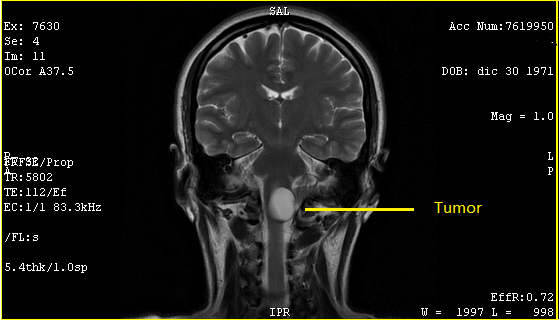

Mi mamá y yo estábamos sentadas de frente al doctor, al lado de la pantalla que usan para ver las placas. Al principio, checó las radiografías y me confirmó cuatro hernias: dos en cervicales y dos en lumbares. Posteriormente, colocó la resonancia magnética, se acercó a la pantalla unos segundos, como tratando de descifrar algo y sin voltear a verme y con la mirada fija en la pantalla, me dijo: "Me llama la atención el tumor que hay en esta área", y, apuntando con el dedo a la pantalla, señaló: "Mire, justo aquí, donde están las cervicales, muy cerca del cerebelo. ¿Ve esta masa blanca? Ese es un tumor que, por cierto, está grande. ¿Cuánto lleva con ese tumor?".

No pude ver ni entender lo que me estaba mostrando, esos estudios siempre me han parecido confusos: yo solo veo manchas blancas y negras, pero obvio él debía de estar en un error, con toda firmeza le dije: "¡No,doctor!, usted debe de estar equivocado, yo no tengo ningún tumor". Volteé a ver a mi mamá y estaba pálida; le repetí: "No, doctor, no entiendo lo que me está diciendo. Le repito: yo no tengo ningún tumor", pero a él pareció no importarle mi respuesta y sin quitar el dedo de la pantalla y viendo fijamente la mancha, dijo: "Le repito:¿ve esto blanco? Este es un tumor y está grande".

Dos días después, por recomendación y presión, conseguí una cita urgente con un neurocirujano del mismo hospital. Un hombre de mediana edad, de semblante relajado y afable pero de pocas palabras, me recibió y me preguntó cortante por qué había acudido con él. Le conté del ortopedista y le mostré los estudios. Lo confirmo y agregó: "Por la posición donde está alojado el tumor, junto al cerebelo, muy cerca del cuarto ventrículo, es peligroso ya que es de gran tamaño y está bloqueando el paso de líquido cefalorraquídeo a la columna". Obvio no entendí nada de lo que dijo en ese momento, sus palabras no tenían ningún significado para mí, pero por la expresión de su rostro entendí que era algo serio.

El 13 de agosto de 2019, ya con la resonancia de cráneo y los papeles del seguro, acudí con el doctor. Después de verlos me confirmó: "Es un tumor (quiste) benigno con el que nació. Se desconoce por qué se forman, pero una teoría es que son residuos de placenta que se quedan cuando se forma el producto en el vientre. Eso no es un tema, mi principal preocupación es su ubicación y tamaño mide: 3.3cm x 2.1cm x 1.7cm y se comunica con el cuarto ventrículo, y está obstruyendo el paso de líquido cefalorraquídeo a la columna". Me advirtió: "Va a ser un procedimiento muy doloroso, así que debes de estar consciente de ello". Llenó los papeles del seguro con carácter de urgente, con el diagnóstico: Tumor de comportamiento incierto o desconocido en el encéfalo y del sistema nervioso central.